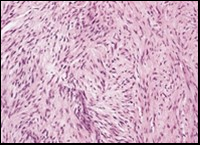

The neoplasm frequently infiltrates abutting skeletal muscle. Occasionally, tumefaction denominates hyper-cellular foci, tumour necrosis, cellular or nuclear atypia and mitotic figures, features which are characteristic of intermediate to high grade sarcoma. Localized tumour reoccurrence may be hyper-cellular with enhanced mitotic activity 4, 5. On ultrastructural examination, fibroblastic differentiation is exemplified 5. Figure 1, Figure 2, Figure 3, Figure 4, Figure 5, Figure 6, Figure 7, Figure 8.

Figure 2.Low grade fibromyxoid sarcoma exemplifying intermingled foci of fibrous and myxoid regions of spindle-shaped cells with minimal pleomorphism and absence of mitosis (10).